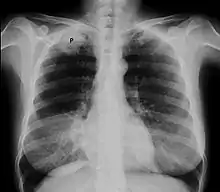

Chest X-ray showing a Pancoast tumor (labeled as P, non-small cell lung carcinoma, right lung), from a 47-year-old female smoker.